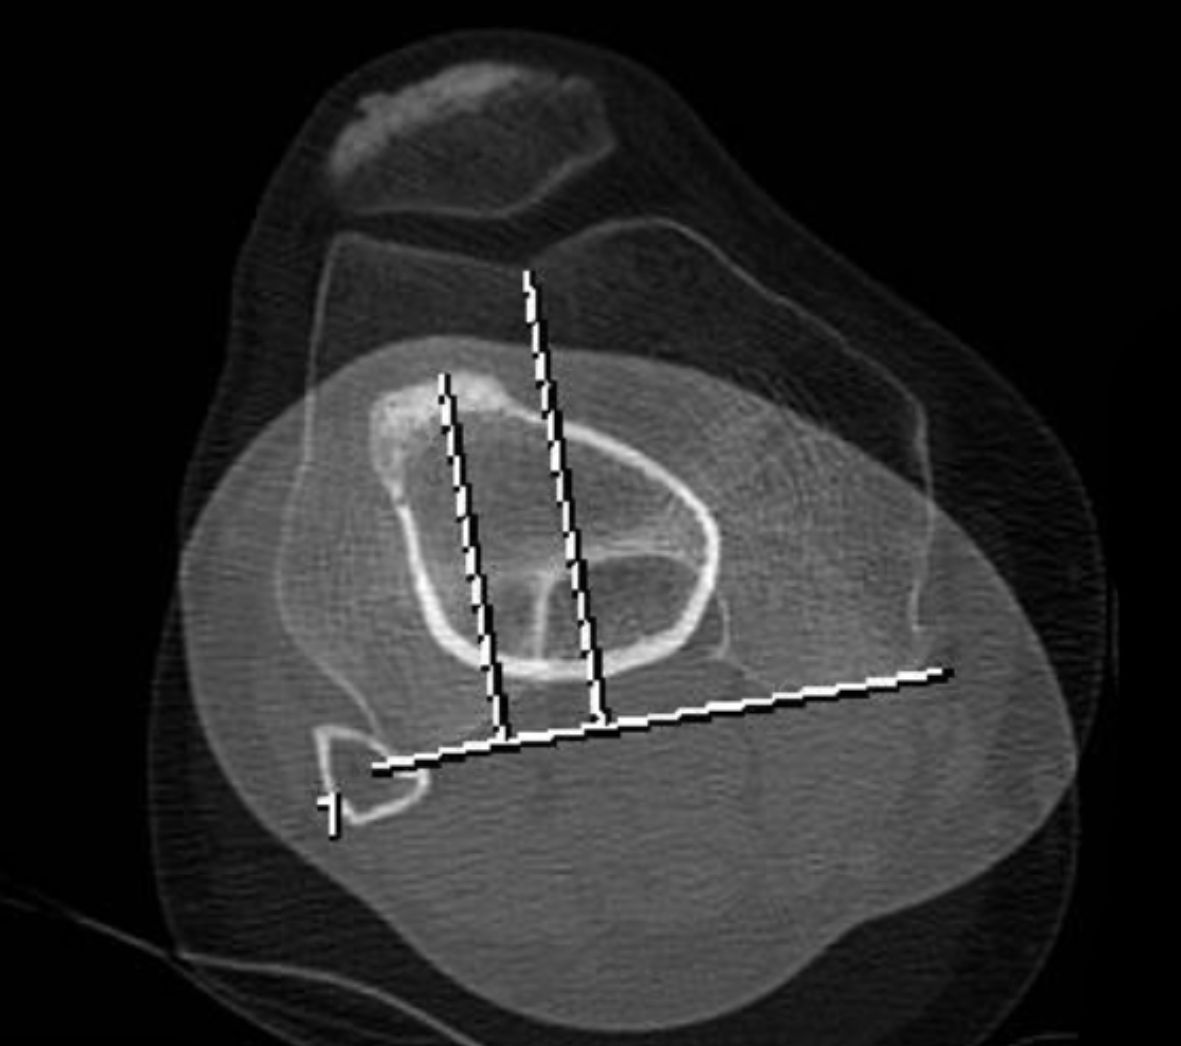

The TT-TG distance can be measured as the mediolateral distance between the midpoint of the insertion of the patellar tendon and the trochlear groove (Figure 1).

Tibial torsion is measured between a reference line tangential to the posterior border of the tibial plateau right above the tip of the fibular head, and with a second line that runs through the center of the medial and lateral malleolus [5]. (Figure 2)